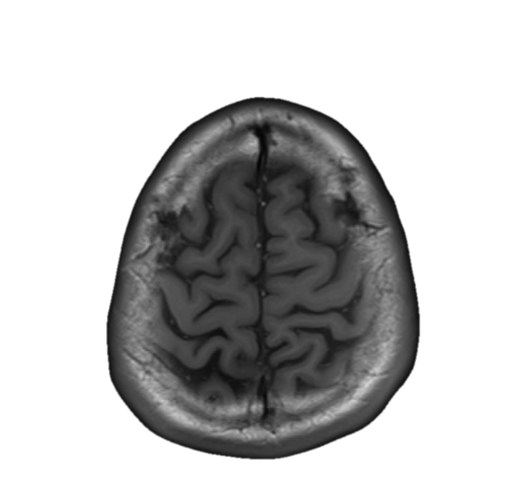

中心溝、中心前溝、中心後溝、中心前回、中心後回のMRI画像における解剖

主に脳梗塞診断などで重要な中心溝、中心前溝、中心後溝、中心前回、中心後回のMRI画像における解剖(CTでも使えます。)をご覧いただけます。